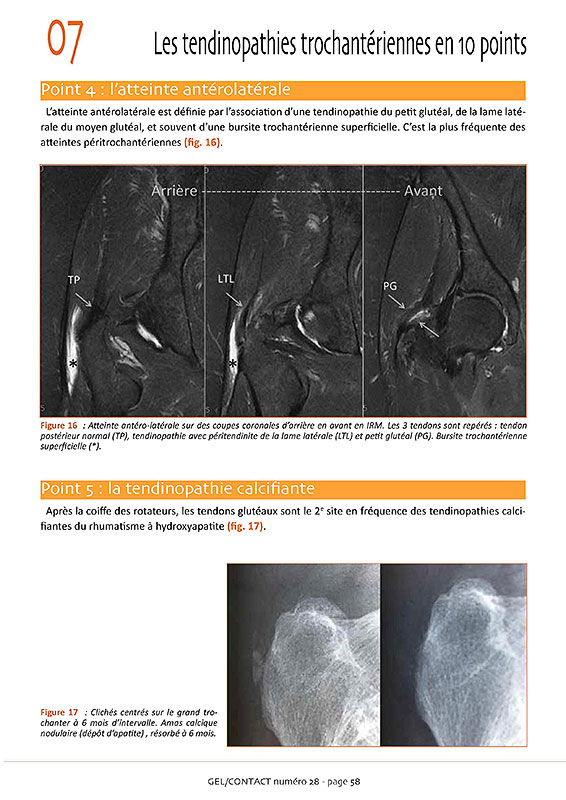

Gel Contact N°28

JUIN 2019